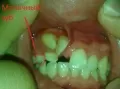

Мне 24 года, главная моя проблема — это выпирающие вперед верхние боковые резцы, а первые резцы с задней стороны полностью забломбированы на штифтах. Каким образом мне можно исправить кривизну передних верхних зубов? Носить брекеты желания нет.

Здравствуйте. Подскажите, возможно ли выровнять зубы (кривые только верхняя челюсть) без брекетов? У меня торчат 2 зуба вверху. Можно ли их сточить и наростить искуственные?